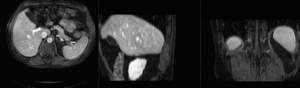

Registration Results (click to enlarge)

unregistered MRI & CT

after linear (affine) registration

after nonrigid registration